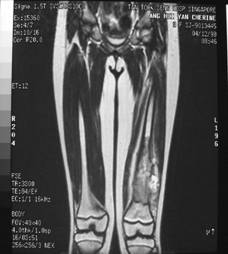

Pre Op

>X-ray (Left femur)

osteolytic lesion

• (?) osteosarcoma